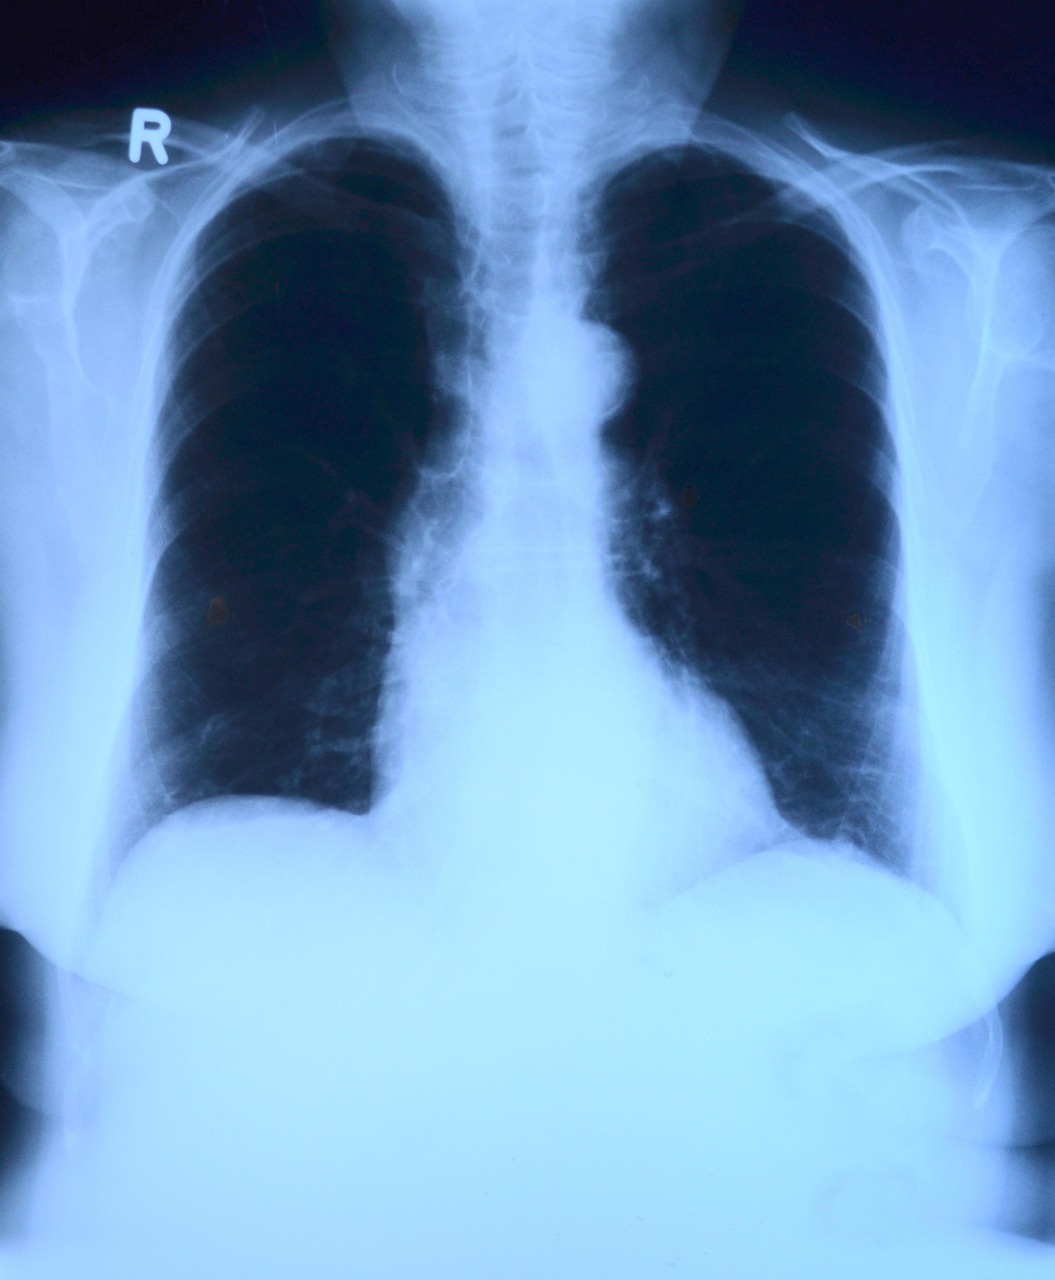

폐암은 국내 암 사망률 1위를 기록할 정도로 치명적인 암입니다. 흡연이 가장 주요한 위험 요인으로 알려져 있으나, 최근에는 비흡연자에게서도 발병 사례가 증가하고 있습니다. 폐암은 크게 소세포폐암과 비소세포폐암으로 구분되며, 각각의 성장 속도와 치료 반응이 다릅니다. 초기 폐암은 대부분 무증상으로 진행되며, 기침이 오래 지속되거나, 가래에 피가 섞이거나, 호흡곤란, 흉통 등의 증상이 나타날 경우에는 이미 상당 부분 진행된 경우가 많습니다. 또한 체중 감소나 만성 피로 등 일반적인 증상도 동반될 수 있어 감기나 피로로 착각하기 쉽습니다. 조기 발견이 어렵기 때문에 정기적인 흉부 X-ray, 저선량 CT 검사가 중요한데, 특히 55세 이상이거나 흡연 경력이 있는 사람은 고위험군으로 분류되어 매년 검진이 권장됩니다. 폐암의 치료는 암의 위치, 크기, 전이 여부에 따라 수술, 항암치료, 방사선 치료, 면역치료 등이 병행됩니다. 무엇보다 흡연자는 금연이 최우선이며, 간접흡연도 피하는 것이 중요합니다. 실내 공기 질 관리, 유해 물질 노출 최소화 등도 폐암 예방에 큰 도움이 됩니다.